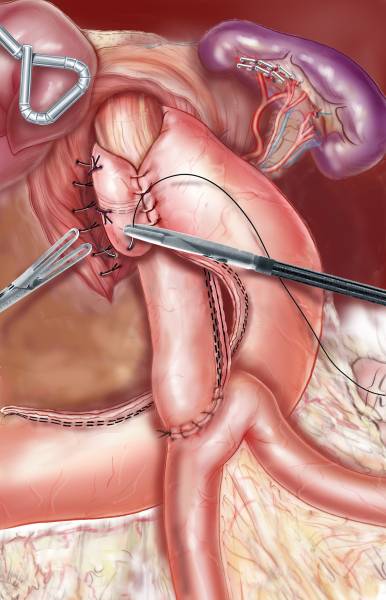

Quelle Solution en cas de reprise de poids après by-pass ? le by-pass sur by-pass

Les chirurgiens bariatrique du groupe MUST à Paris sont spécialisés dans la gestion des cas complexes en chirurgie bariatrique. De plus en plus de patients ayant déjà beneficié d un by-pass consultent car ils ont repris des poids progressivement et n ont pas de solution efficace pour reperdre du p...